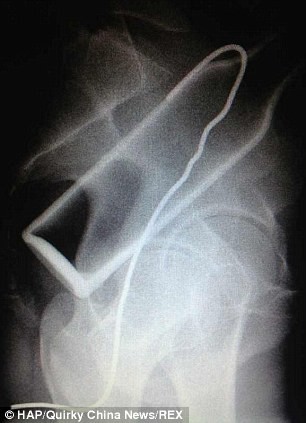

Un hombre que se introdujo una botella en el recto, debió pedir ayuda médica luego de intentar solucionar el problema por su cuenta. Para ello, trató de "pescar" el envase con un gancho de alambre, pero segundo objeto también quedó atrapado dentro de sus intestinos.

El individuo, según consigna MailOnline, acudió a un hospital de la ciudad de Fuzhou, quejándose de dolores de vientre. Ante la evidencia, confesó que se había introducido la botella, y que luego, asustado, había maniobrado sin éxito con el gancho.

Los médicos debieron recurrir a la cirugía para extraer ambos objetos, y durante el procedimiento descubrieron que el intestino grueso del paciente había recibido rasguños en varias partes, causados por el gancho de metal.